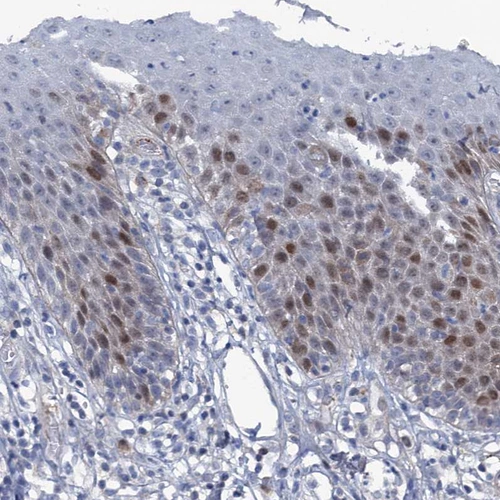

Immunohistochemical staining of human tonsil shows weak to moderate nuclear positivity in germinal center cells.